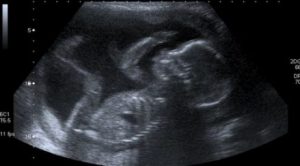

Varje mor är dock införstådd med att hon har en lång väntan framför sig. Under de kommande nio månaderna måste hennes kärlek för sitt ofödda barn nöja sig med ultraljudsbilder på en svartvit skärm innan hon kan träffa sin son eller dotter öga mot öga, och upptäcka färgen på dess hud, hår och ögon.